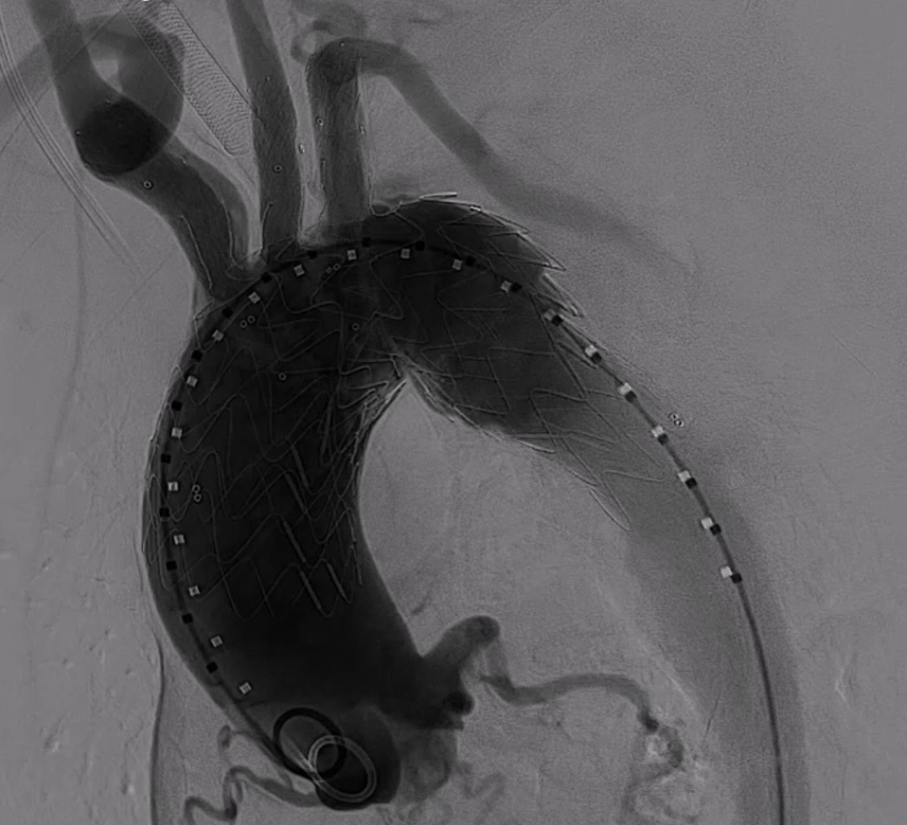

术后造影显示,主动脉支架定位精准,三分支支架内血流通畅,夹层内仅有少量膜渗情况。从手术即刻效果来看,该治疗方案达到了预期目标,有效修复了主动脉夹层,恢复了血管的正常解剖结构和血流动力学状态。

患者术后全麻苏醒过程顺利,术后常规核磁共振(MRI)检查发现存在少量新发无症状脑梗病灶。考虑到多种因素,该脑梗病灶可能与手术操作过程中的微血栓脱落、血流动力学改变等相关。不过,患者整体术后恢复状况良好,胸痛症状得到明显改善。目前,患者已进入规范随访阶段,等待术后 6 个月进行血管造影(CTA)复查,以进一步评估手术远期效果及血管恢复情况。